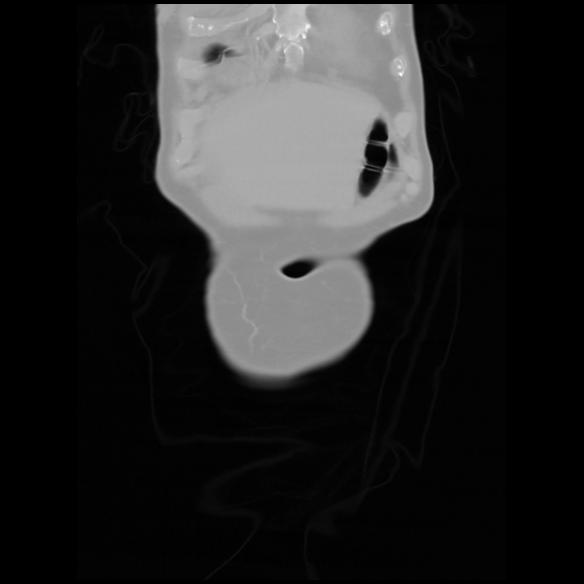

6 CUERPO,CE,Coronal,3.000,CUERPO,Coronal,